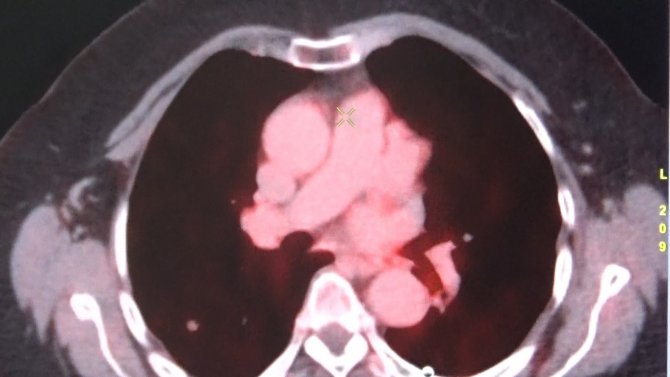

Diyarbakır Gazi Yaşargil Eğitim ve Araştırma Hastanesinde 2010 yılından bu yana hizmet veren Nükleer Tıp Bölümünde birçok hasta radyoaktif tedavisiyle şifa buluyor. Son nükleer tıp teknolojileriyle her türlü sintigrafik görüntülemenin yapıldığı bölümde, kalpten akciğere, karaciğerden kemik ve böbreğe kadar geniş bir alanda teşhis için SPECT/CT, SPECT, PET/CT ve FAPI cihazları kullanılıyor. Bölgenin en büyük etkin nükleer tıp merkezlerinden olan Gazi Yaşaragil Eğitim Hastanesinde 3 doçent doktor ve 5 uzman doktor ile Nükleer Tıp Bölümü hizmet veriyor. Nükleer Tıp Bölümünün sadece sintigrafik görüntülemeden ibaret olmadığını belirten Nükleer Tıp Uzmanı Doç. Dr. Halil Kömek, hastalığın yarısı oranında tedavi ile ilgilenen bir bilim dalı olduğunu söyledi. Kömek, "FDG PET/CT ile onkolojik tüm vücut görüntüleme yapan cihazlarımız mevcut. Prostat kanserleri için 68Ga-PSMA, nöroendokrin tümörleri görüntülemesi için 68Ga (Galyum68)-Dotatate ve ülkemizde birkaç merkezde uygulanan TİTCK (Türkiye İlaç ve Tıbbi Cihaz Kurumu) onaylı olduğumuz FAPI (fibroblast aktivasyon protein inhibitörü) ile kolorektal ve gastointestinal kanserlerinin periton yayılımlarında kullandığımız FAPI görüntülemesi yapmaktayız" dedi.

Hastanede yılda 6 bin hastanın tümör taraması amacıyla PET/BT görüntülemesinin yapıldığını söyleyen Kömek, "Hastanemizde ayrıca tiroid kanseri 300 hastaya İyot tedavisi yapılmakta. Yılda 400 hastaya da Lutesyum tedavileri, prostat kanserlerinin nöroendokrin tümörlerinin ya da ağrı palyasyonu amacıyla uygulanmaktadır. Açılımını yaparsak eğer, radyoaktif madde ile işaretlenmiş bir reseptör bağlacını hastanın vücuduna enjekte ediyoruz ve sadece tümörlü alanları tutup tedavi ediyor. Herhangi bir yan etkisi olmadan sadece tümöre spesifik reseptörlere bağlanarak tedavi edildiği için, hedeflenmiş radyoterapi dediğimiz sistemi kullanıyoruz. Bunun yanı sıra yılda yaklaşık 300 hastanın da hipertiroidi tedavisini yapmaktayız" şeklinde konuştu.